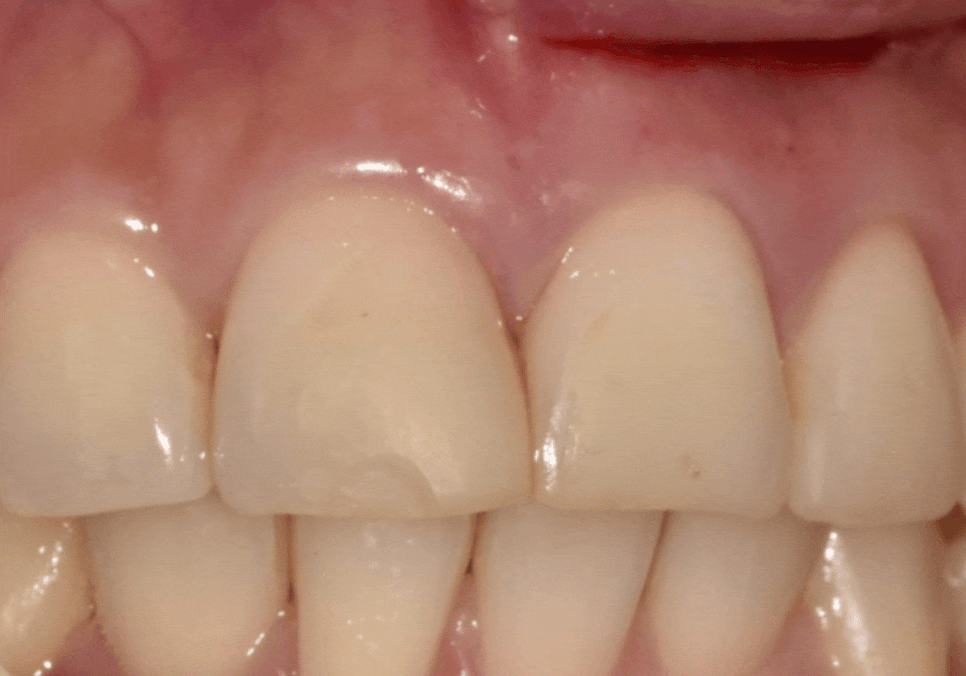

레진 변색을 해결해드리고

약 5개월이 지나

환자분이 다시 내원하셨습니다.

식사 중

앞니 끝부분이 살짝 깨졌다고 하셨는데요.

사진으로 보면

아주 크지 않아 보일 수 있습니다.

하지만 앞니는

보이는 부위이다 보니

아주 작은 깨짐도

환자분이 느끼기에는

크게 느껴질 수밖에 없는 것 같습니다.

이 경우 레진으로

끝부분만 보강하는 방법도 가능하지만,

환자분은 예전에 레진 탈락 경험도 있었고

변색도 한 번 겪으셨던 상황이라

이번에는

조금 더 오래, 안정적으로 쓰는 방향을

원하셨습니다.

그래서 치아 삭제를 많이 하지 않는 범위에서

라미네이트를 치료 옵션으로 설명드렸습니다.